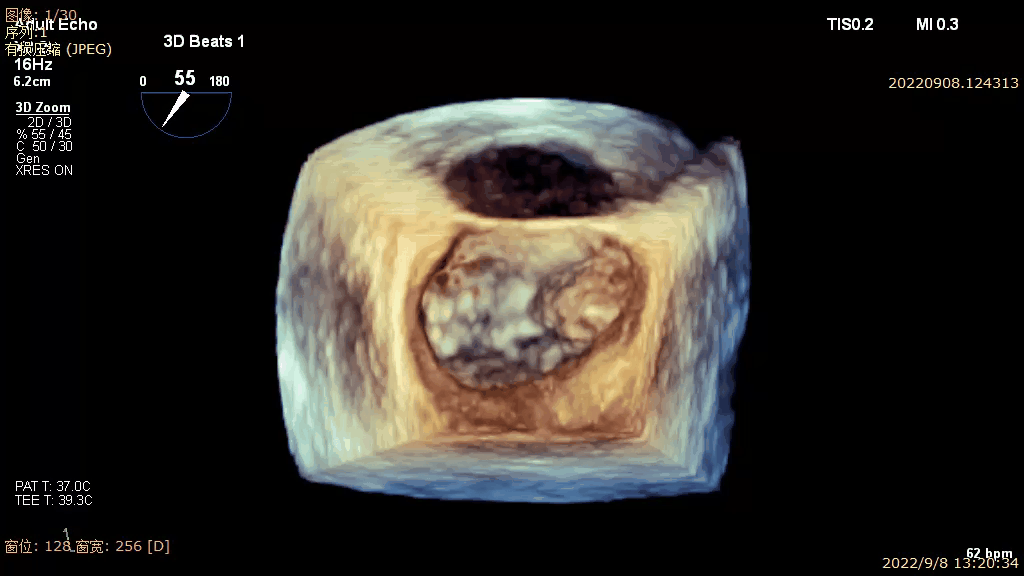

术前TEE 3D VIEW

二尖瓣病变Carpentier II型,DMR,二尖瓣A3及内交界瓣叶脱垂,心脏扩大,病变部位靠内侧,连枷间隙约8mm,瓣口面积5cm²,3区前叶长17mm,后叶长10mm。MR4+,反流束来自于3区,呈偏心性,指向1区,沿后叶走行;VC6.3 mm。PGmean 1mmHg。房间隔穿刺空间约4.5cm。